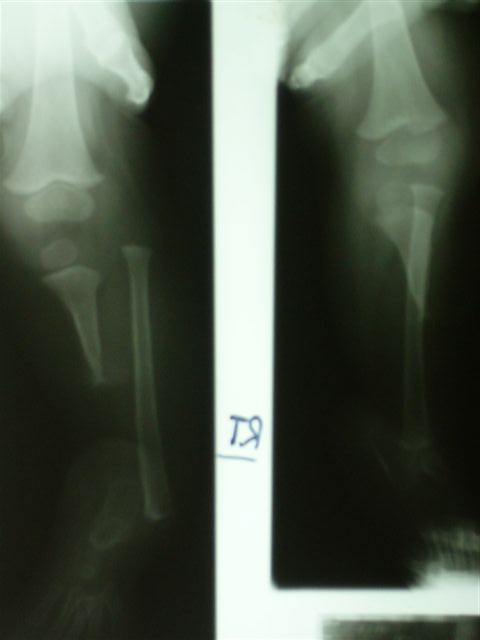

Уважаемые коллеги,Ребенок 4 лет с врожденной гемимелией б/б кости справа.

Первые две операции сделаны в годовалом возрасте - проксимальный тибио-фибулярный синостоз и транспозиция дистального отдела малоберцовой кости на таранную кость.В настоящее время - пользуется ортопедической обувью, компенсирующей 6 см укорочение конечности, нога опороспособна и безболезненна.Рг - компенсаторная гипертрофия малоберцовой кости, состоявшийся синостоз б/б и м/б.Вопрос: когда следует начинать коррекцию длины в аппарате?Заранее спасибо за рекомендацииЕвгений И Чекашкин

Сейчас ребенку 4 года, укорочение 6 см. Существует мнение о начале коррекции в аппарате не ранее 5 летнего возраста, кость становится прочнее, меньше риск миграции спиц. Хотя и на современных Рг кость выглядит вполне *зрелой*.

К сожалению, после осмотра весь пакет с Рг родители забрали с собой. Описание Рг: В принципе, голеностопного сустава (как анатомического образования) у ребенка не было сформировано, поэтому при росте м/б кости происходило * выталкивание* стопы медиально с её супинацией (начальные снимки). Поэтому, чтобы яредотвратить усугубление деформации стопы, мы решили сопоставить м/б кость с таранной и фиксировали спицами и гипсовой повязкой. На том этапе сознательно на артродез не пошли, рассчитывая, что фиброз в зоне контакта костей позволит сохранить межфрагментарную подвижность, облегчающую ходьбу, и не ошиблись. На данный момент подвижность в зоне контакта малоберц.-таранная костей в пределах 30 градусов (пассивные движения) активные практически отсутствуют, можно думать и о мышечной аномалии- выражены только сгибатели и пронаторы стопы.

Я планирую удлинять за счет голени - остеотомия на уровне тиб-фиб синостоза, поскольку удлинение за счет бедра приведет к разновеликим коленкам, длину мы восстановим, а вот соосность пострадает. Следующий осмотр назначил через 6 мес - чтобы оценить природную скорость продольного роста правой голени и более определенно планировать коррекцию или пойти на гиперкоррекцию. Что вы думаете по этому поводу?